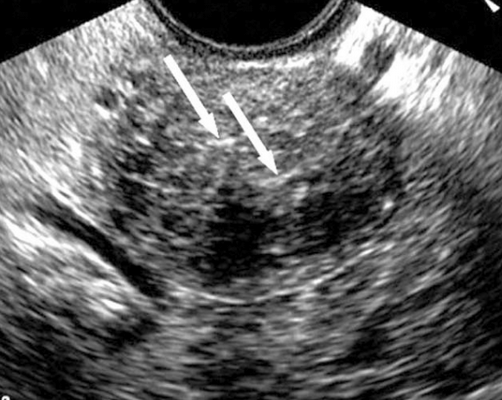

Как правило, неходжкинская лимфома располагалась в малом тазу экстраперитонеально, имела плотную структуру и гетерогенное содержимое в виде гиперэхогенных и гипоэхогенных участков (рис 4). Допплерография показала гиперваскуляризацию опухоли.

Рис.4. Метастазы лимфомы: хорошо определена гетерогенная опухоль с множественными гиперэхогенными включениями (1) и с гипоэхогенными участками (2).